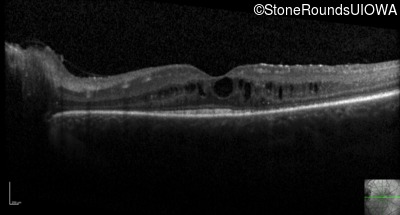

Optical Coherence Tomography - Left - 20/50 -3

Exemplar / OCT Stack

OCT Stack